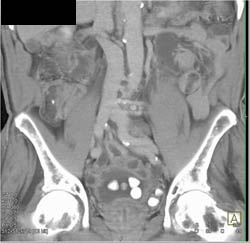

Bladder Cancer